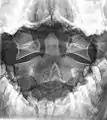

مهره آکسیس در یک تصویر رادیولوژی